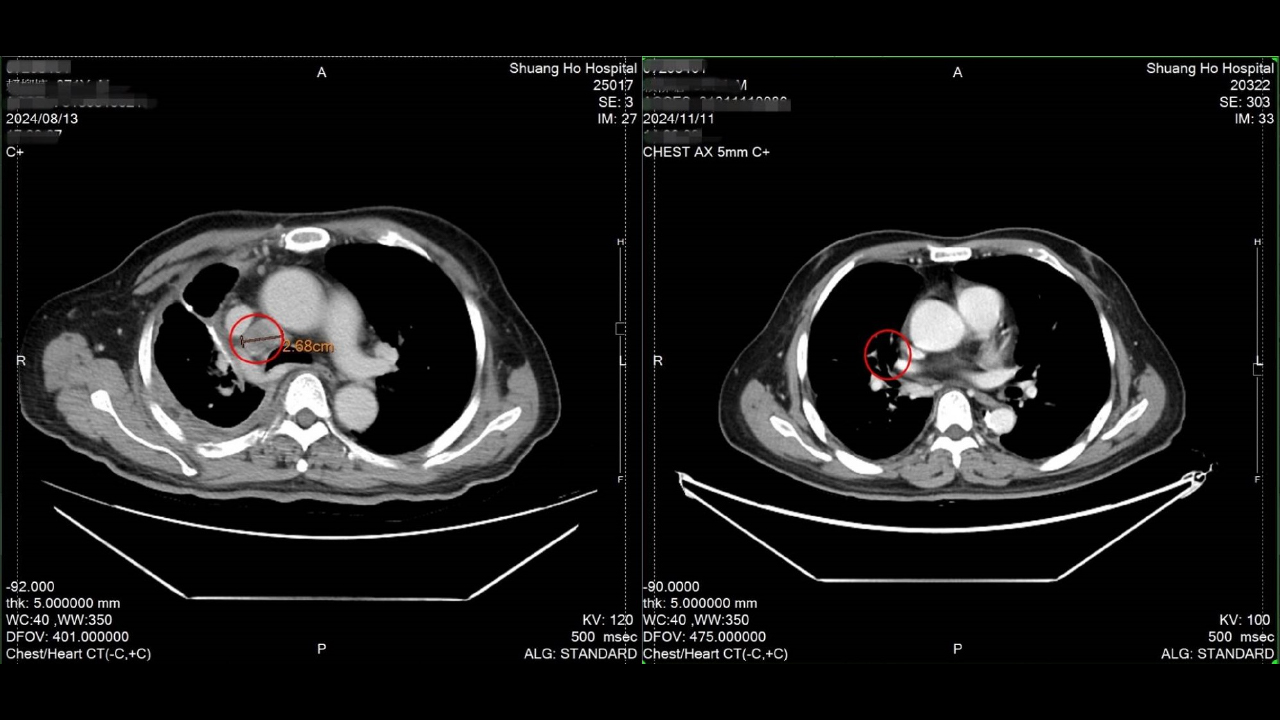

雙和醫院血液腫瘤科主任謝燿宇醫師指出,從治療前的影像檢查中可明顯看到肺部腫瘤持續擴大,除透過基因篩檢找出合適的標靶藥物外,合併搭配每劑間隔兩周,共六劑的DC-CIK細胞回輸治療也是關鍵,後續透過電腦斷層檢查可明顯看到腫瘤縮小,部分腫瘤甚至消失;除療效顯著外,更重要的是幾乎無副作用產生,精神與體力並無影響,未來只需按照醫囑定期回診即可。

↑圖說:經DC-CIK細胞治療治療後檢查發現腫瘤明顯縮小,部分腫瘤甚至消失。(左圖治療前,右圖治療後)(圖片來源:雙和醫院提供)